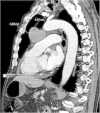

Neuroblastoma is considered a pediatric malignancy as over 95% of cases are diagnosed in patients ≤10 years old. This cancer is extremely rare in elderly patients. We conducted a Surveillance, Epidemiology, and End Results (SEER) database analysis in the USA between 1973-2007 that revealed only 35 elderly patients (>60 years of age) with neuroblastoma of whom only 2 patients had primary mediastinal neuroblastoma. There is a paucity of treatment and survival outcomes data for the elderly owing to the rarity of neuroblastoma in this population. Currently there are no standard guidelines or protocols for treatment of adult neuroblastoma. We report a rare and challenging case of an 86-year old patient presenting with mediastinal neuroblastoma and syndrome of inappropriate antidiuretic hormone secretion (SIADH) successfully treated with resection. Herein, we also provide a review of the literature and updated survival data on neuroblastoma based on results of our SEER database review.